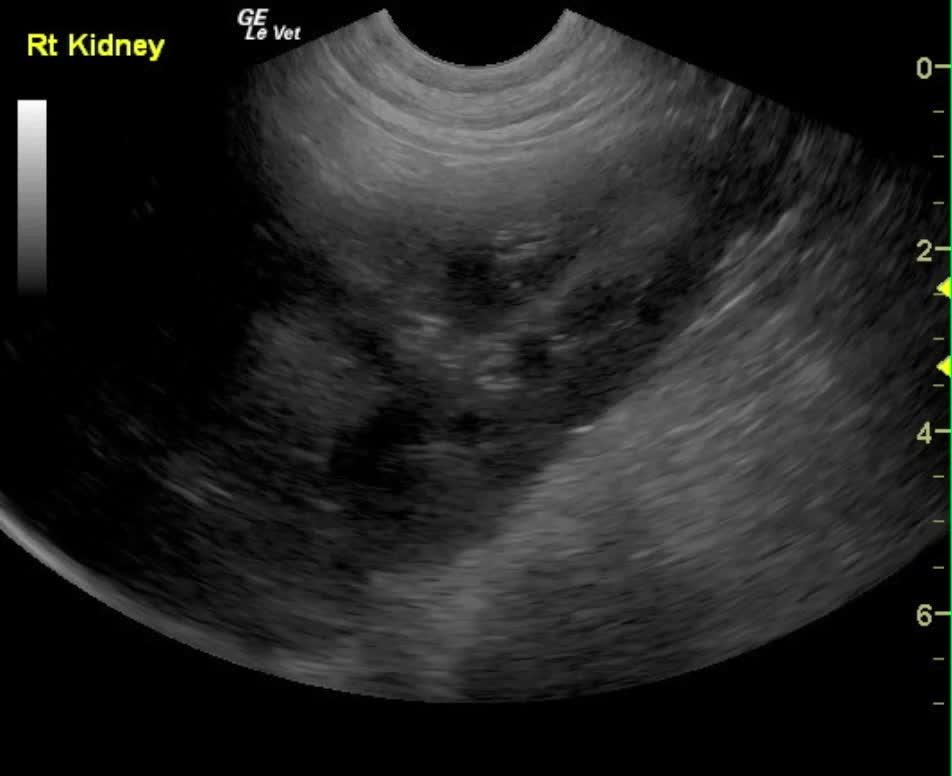

The kidneys in this patient had a persistent, slightly irregular contour, with the left kidney demonstrating slight pyelectasia (0.26 cm). The urinary bladder, trigone and pelvic urethra presented normal wall thicknesses with anechoic urine and normal tone. The urinary bladder revealed slight calculus at 0.23cm, yet was not shadowing. No evidence of inflammatory or neoplastic changes were noted.